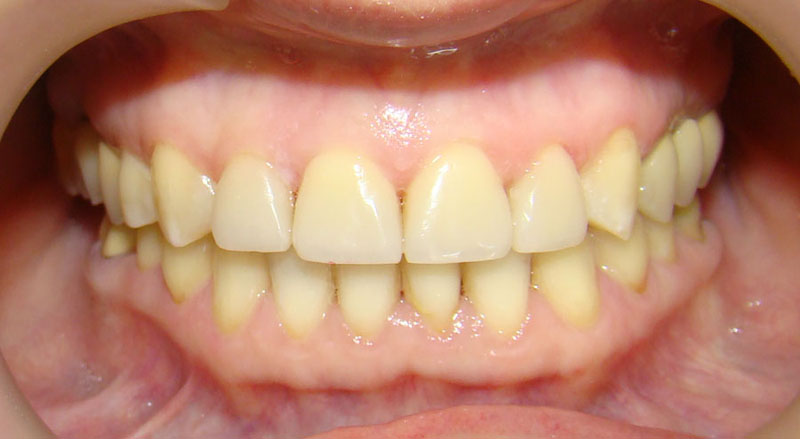

Девушке 14 лет. Получилось все исправить без удаления зубов

А это уже молодой человек 10 лет. Тоже получилось справиться без удаления. Хоть оно и было показано. Но мальчик очень упорно носил специальные аппаратики и резиночки. Покажу со всех сторон. Этот случай победил в конкурсе на конференции